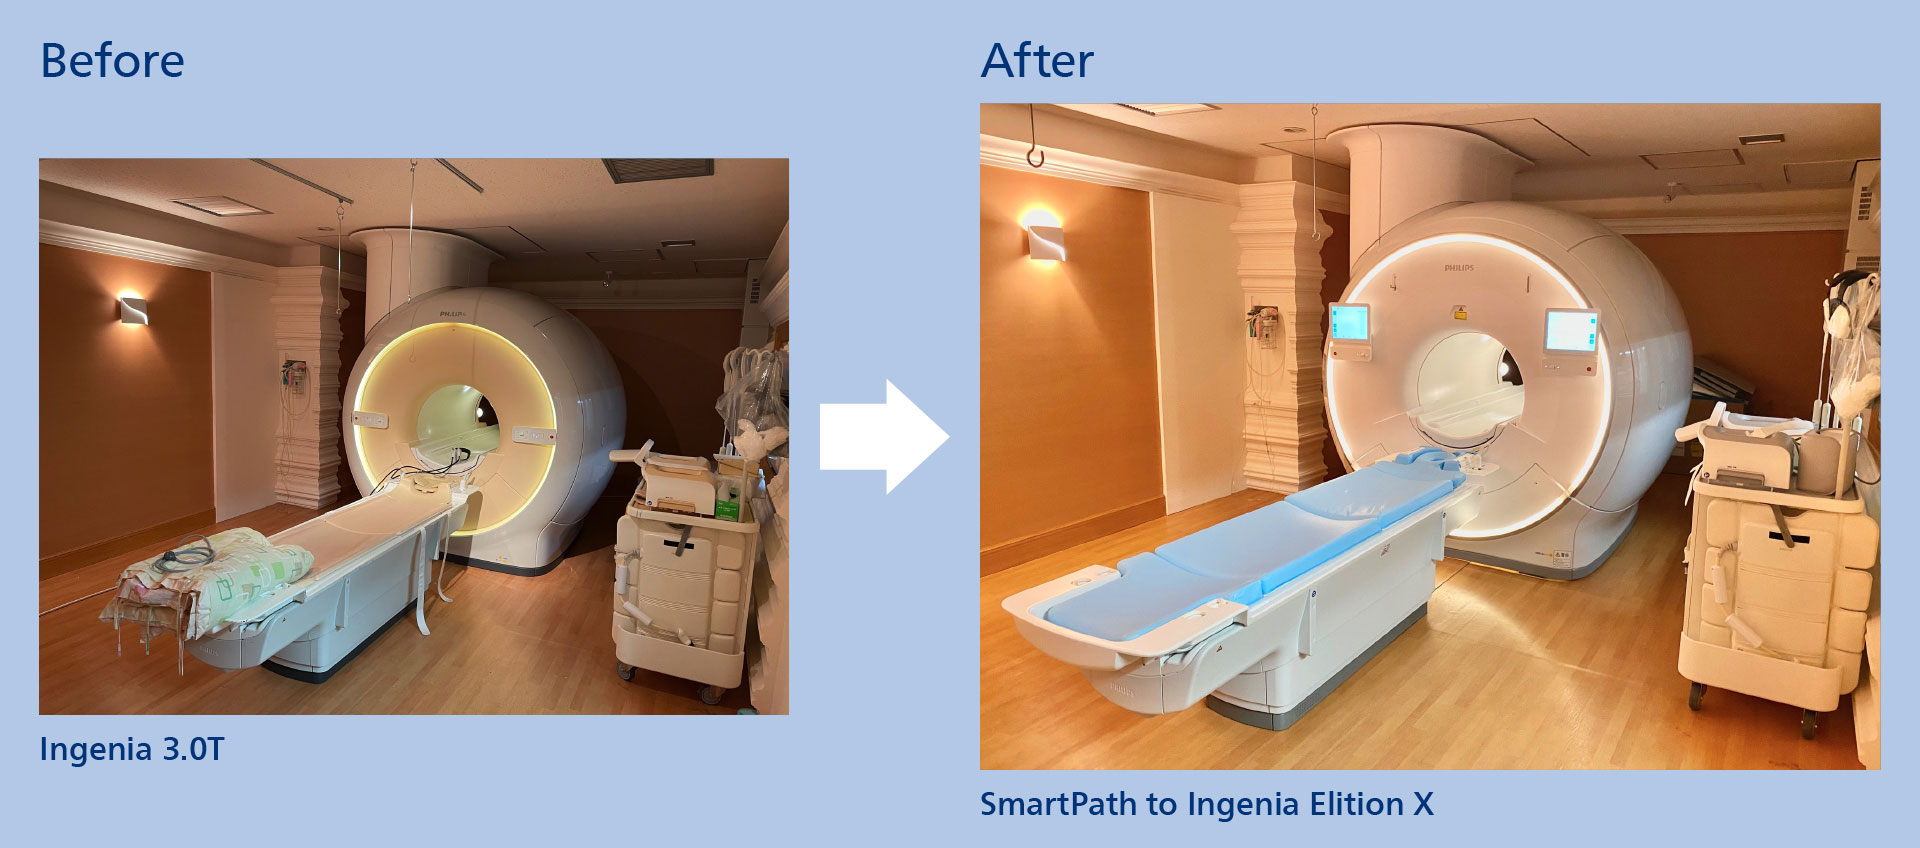

When their Ingenia 3.0T was eight years old, Sannodai Hospital was interested in the newer Ingenia Elition X. The hospital opted for SmartPath to Ingenia Elition X: instead of buying a completely new system, it could retain their Ingenia magnet, while all other hardware and software was replaced. This alternative to buying a complete new system saves money and limits the downtime. Moreover, it gave clinicians the powerful Elition 3.0T platform, offering cutting‐edge MR imaging techniques.

The right offer at the right time

The ambition of Sannodai Hospital (Ishioka City, Japan) is to provide the most advanced medical service to its many patients with the goal of early diagnosis and treatment, especially in emergency care. When the hospital’s radiologists had enjoyed eight years of exceptional MRI scanning with their Ingenia 3.0T system, they began thinking about replacing that system in a few years. Then in 2021, they learned about SmartPath to Ingenia Elition X, the option to upgrade their MRI system to a high-end Elition X, keeping their existing magnet and getting new software and hardware, providing high levels of diagnostic confidence.

Hospital administrators and radiology department officials knew that – compared to a full system replacement – the SmartPath upgrade would save on the cost of the system itself and avoid cost related to exchanging the magnet. It would also reduce the downtime during which no patients can be scanned and no revenue is gained.

The hospital began using its new Elition system in December of 2021. Since then, the system has exceeded the expectations of clinicians and technologists.